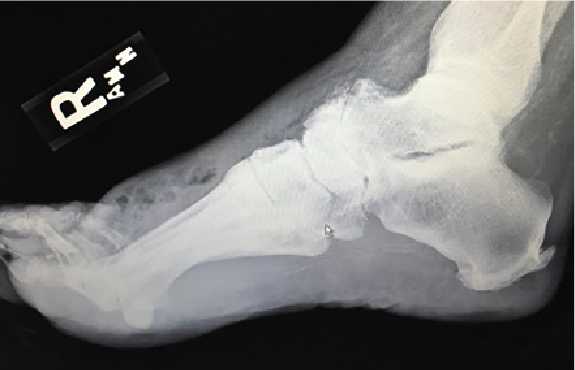

Key Aspects of the Surgical Technique: Case Reports

Case #1 is a 57-year-old female with a past medical history of type 2 diabetes with peripheral neuropathy and hypertension. She stepped on a piece of glass and self-treated with home wound care for several weeks before presenting to the emergency department. Admission took place in December 2012 with a white blood cell (WBC) count of 26,500, erythrocyte sedimentation rate (ESR) of 140, C-reactive protein (CRP) of 29, hemoglobin A1c (HbA1c) 6.3% and negative blood cultures. On physical exam, she had soft tissue emphysema to the dorsal aspect of the right foot from the Lisfranc joint extending proximally to the ankle joint with fluctuance of the second through fifth toes. Radiographs revealed edema and subcutaneous emphysema to the dorsum of the foot across all metatarsal heads (see Figure 1 and Figure 2). A bedside incision and drainage decompressed the abscess.